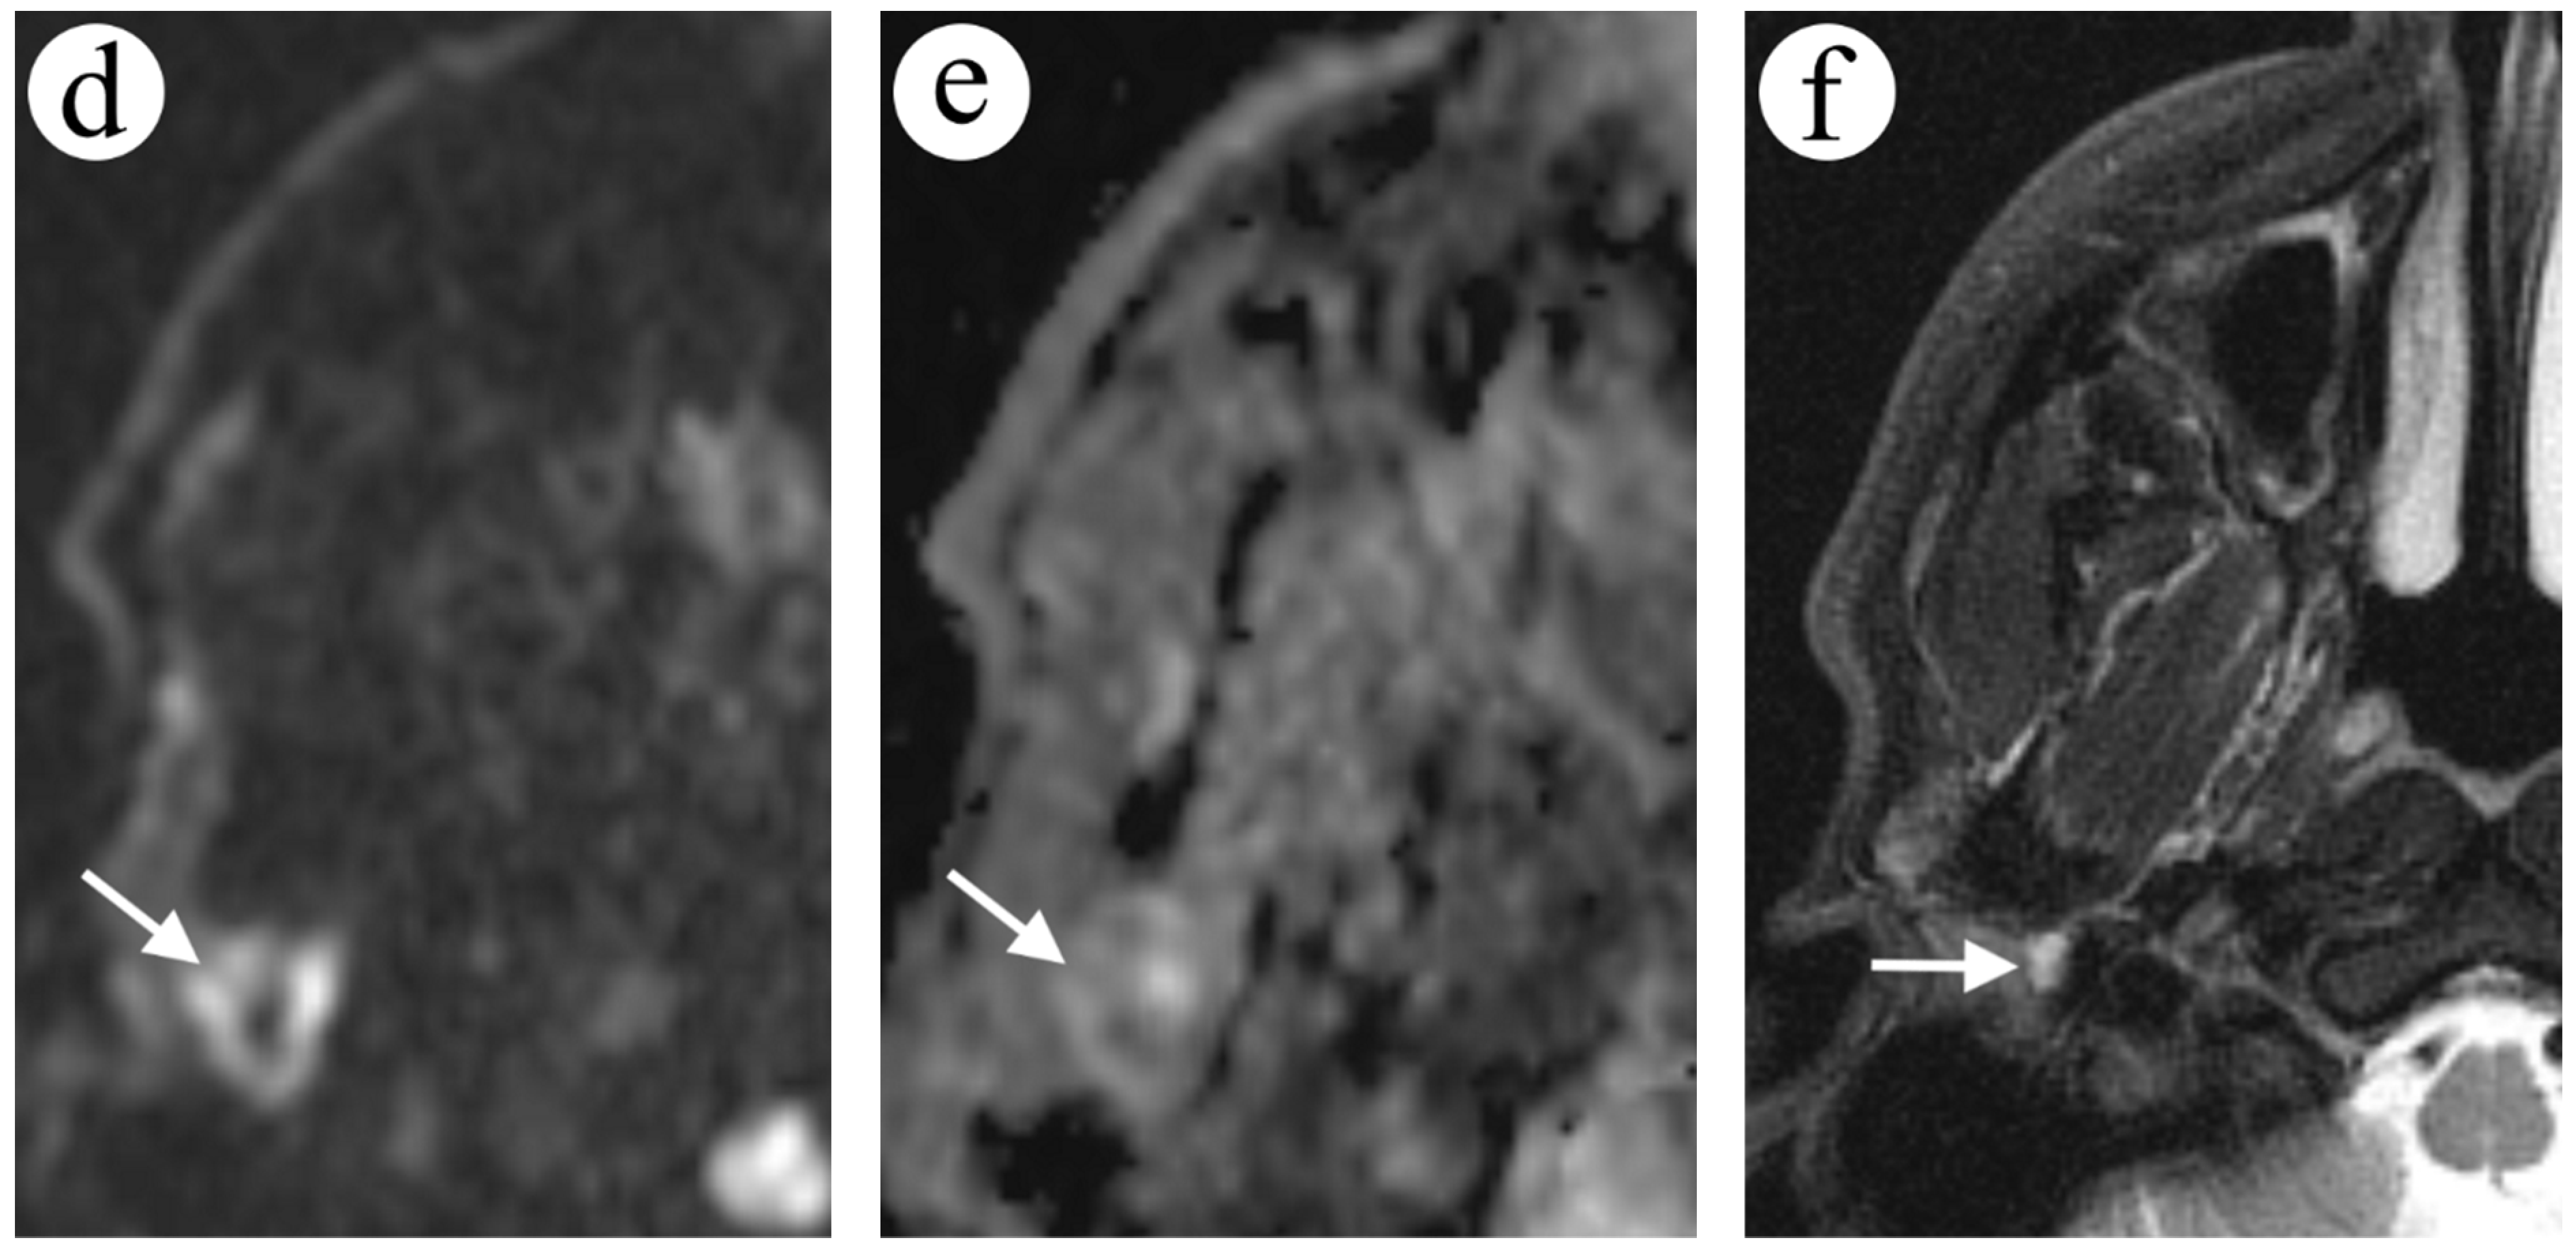

2.4. Case 4